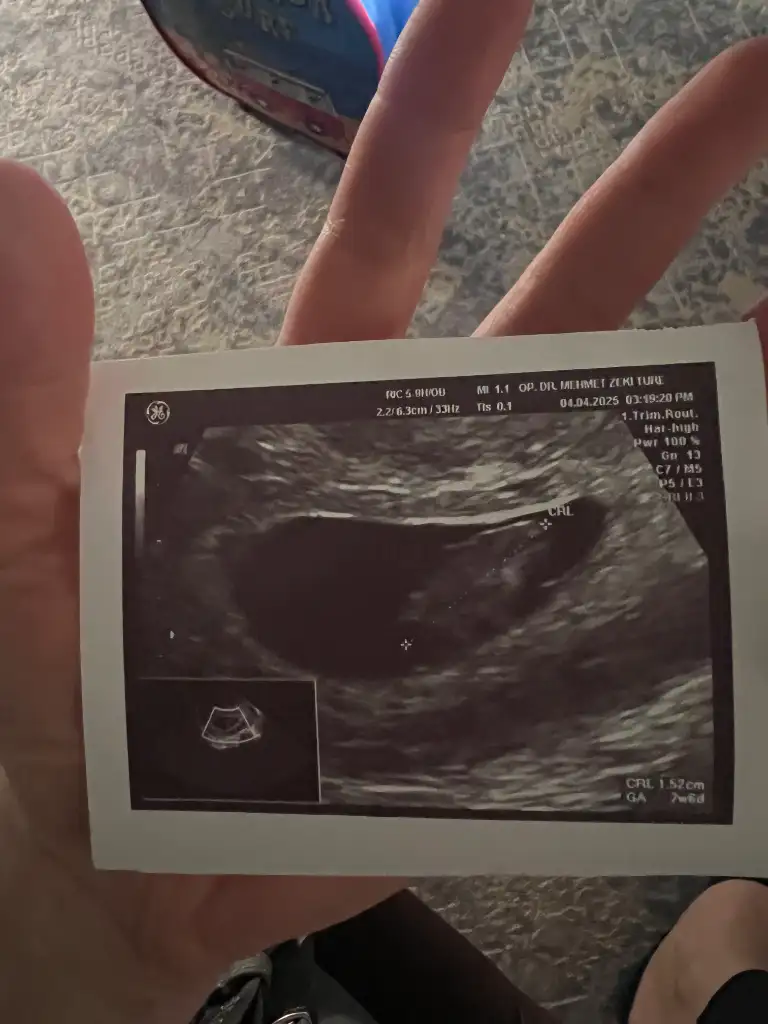

Çok geçmiş olsunMerhaba. Karından ultrasonla bakıldı. SAT’a göre 7+4’teyiz. Benim miniğime de bakar mısınız? Bir düşük tehdidi ile karşı karşıyaydık. 2 gün hastanede yatırdı beni yaramaz![]()

Benim de 7 haftalık görüntüsü karından bu şekilde kesem fazla mı büyük yoksa normal mi buradaki fotoğrafları görünce merak ettimMerhaba. Karından ultrasonla bakıldı. SAT’a göre 7+4’teyiz. Benim miniğime de bakar mısınız? Bir düşük tehdidi ile karşı karşıyaydık. 2 gün hastanede yatırdı beni yaramaz![]()

Merhaba kese bebek boyutu yazar ultrason da kaç yazıyor acaba? Doktorun görüntüyü yakaladığı anla da ilgilidir o durumBenim de 7 haftalık görüntüsü karından bu şekilde kesem fazla mı büyük yoksa normal mi buradaki fotoğrafları görünce merak ettim

merhaba kese boyutu yazmıyor ancak bebek boyutu 9.03mm yazıyorMerhaba kese bebek boyutu yazar ultrason da kaç yazıyor acaba? Doktorun görüntüyü yakaladığı anla da ilgilidir o durum

Bence bir problem yoktur çok büyük gözükmüyor yarın bende doktora gidicem 7+4 olacak size görsel atarım karşılaştırmak istersenizmerhaba kese boyutu yazmıyor ancak bebek boyutu 9.03mm yazıyor